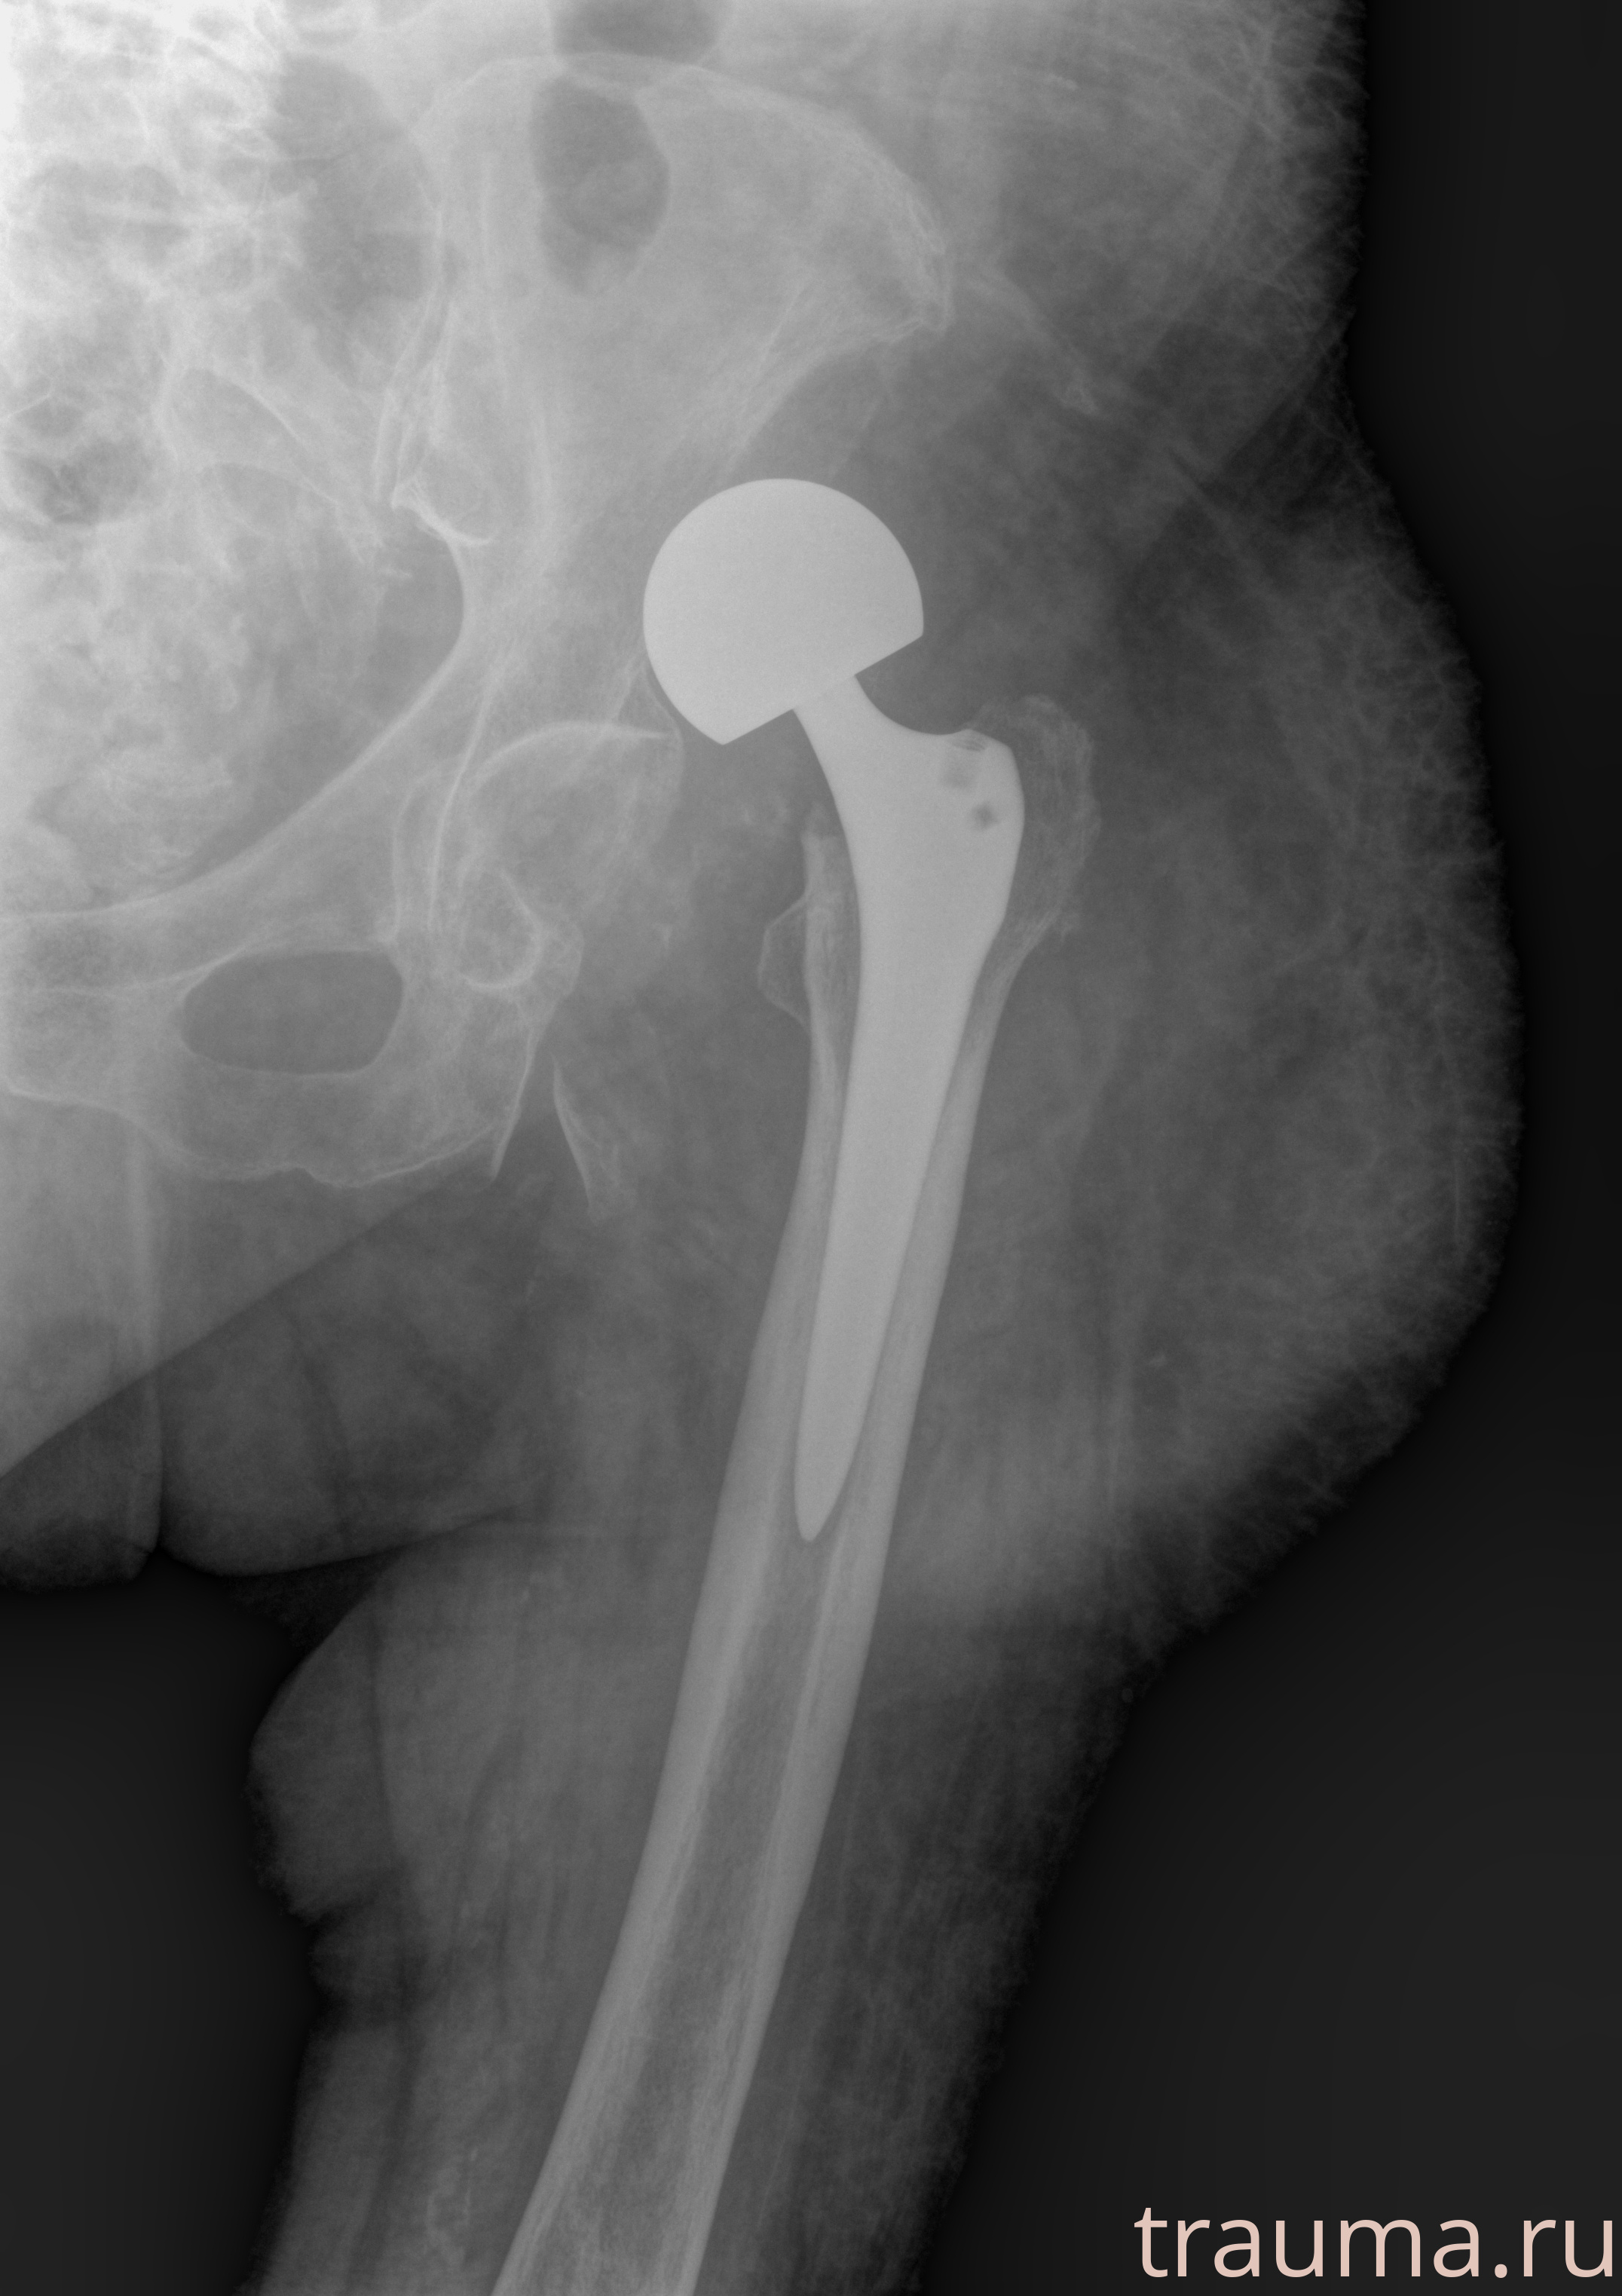

Рентген на дому: по вашему адресу приезжает врач-рентгенолог, травматолог-ортопед с мобильным рентгеновским аппаратом, проводит диагностику травмы или заболевания, делает необходимые рентгенограммы, дает рекомендации по дальнейшему лечению. Получить качественные снимки в домашних условиях возможно благодаря уникальной методике, разработанной МосРентген Центром для института  Склифосовского